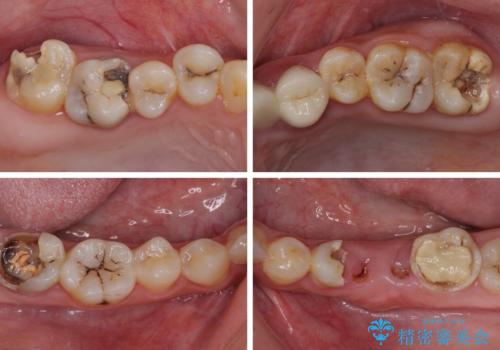

- 奥歯のむし歯を気にして来院された患者様です。

痛みのある歯が多く、根管治療が必要と診断されました。

左下の歯は、クラウンを装着するために必要な高さが足りないため、歯冠長を延長するための外科処置を行うこととしました。

根管治療や歯周外科処置後にフルジルコニアクラウンにて補綴治療することとしました。

自身の口腔内への意識が高くなく、汚れが非常に多い方でした。